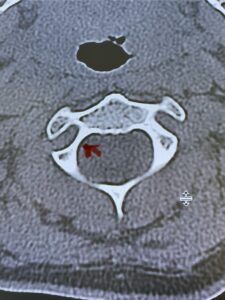

Fig. 4b: Axial T2-weighted cervical MRI demonstrating severe spinal cord compression from atlanto-axial instability (red arrow)

Cervical x-rays revealed a significantly increased atlanto-axial interval (Fig. 5) On review of her imaging studies it was noted that the right C2 isthmus was very thinned by the vertebral foramen (Figs 6a, b, and c) which would make an attempt at placing a C2 pars screw dangerous. A decision was made to perform an occipital-cervical fusion because only possible unilateral fixation and an extensive C1 laminectomy to be performed eliminating a fixation point if a more traditional C1-C2 was performed. Even if C1 lateral mass screws were able to be placed one could only perform a unilateral screw construct fixation to C2. We performed an occipital cervical fusion down to C4 to get enough inferior fixation and C1 laminectomy. The decompression went well. We placed a left unilateral pars screw and bilateral C3 and C4 lateral mass screws. We placed three 12 mm screws in the midline keel (Fig. 7). Postoperatively the patient had all around improvement in her symptoms and did not qualify for rehab. Her post op films at 6 weeks (Fig. 8)